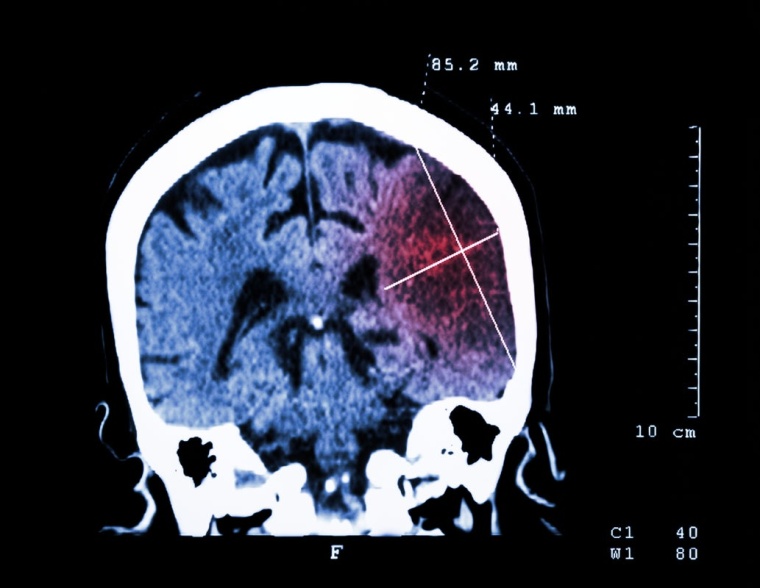

Einem Schlaganfall folgt oft der zweite. Deshalb läuft weltweit die Suche nach Behandlungen, die ein Wiederauftreten von Schlaganfällen verhindern.